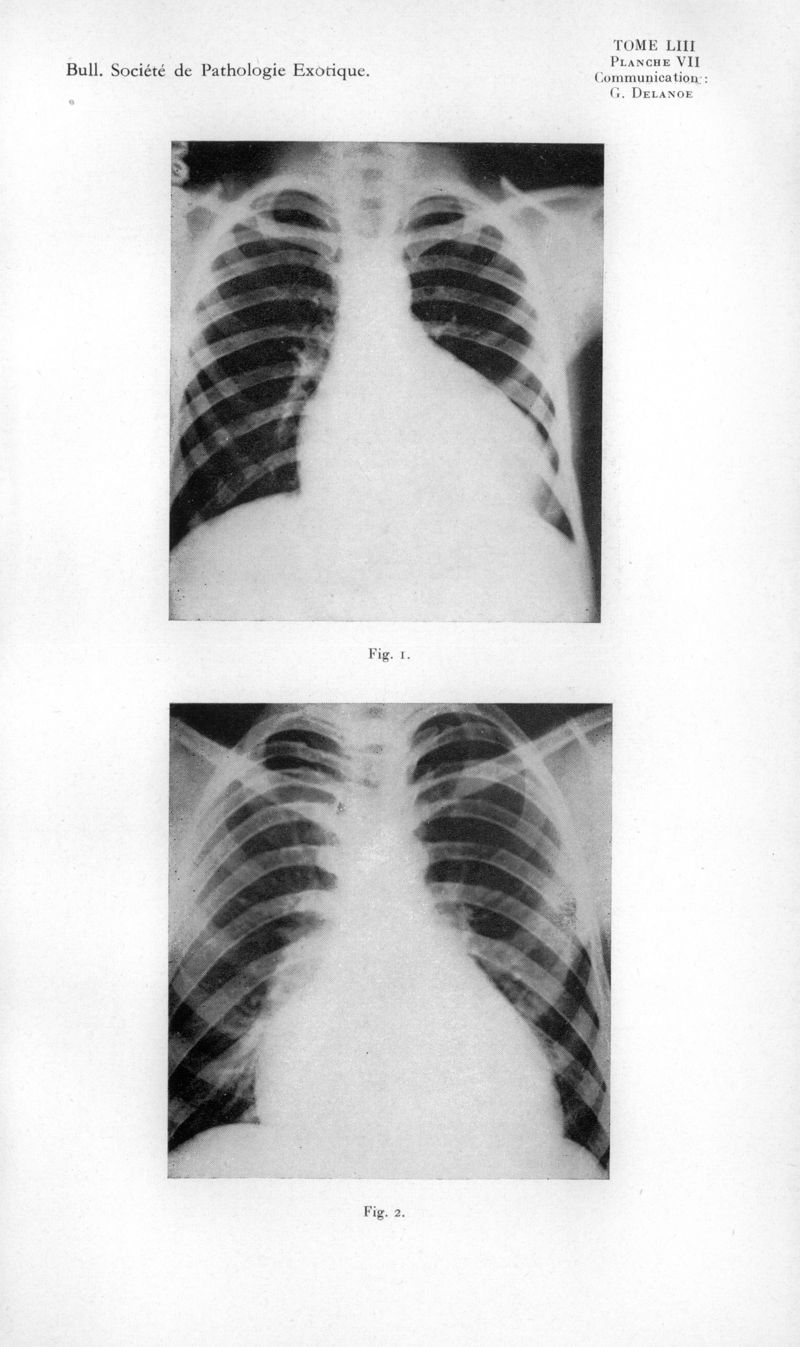

Bulletin de la Société de pathologie exotique et de ses filiales

1960, tome 53. - Paris : Masson, 1960.